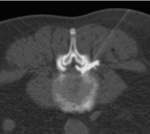

Die durchleuchtungs- und computertomographie-gesteuerte periradikuläre, epidurale und intradiskale Schmerztherapie (PRT) wird im Institut für Radiologie der Augusta-Kranken-Anstalt häufig zur Behandlung von Bandscheibenvorfällen, entzündlichen und degenerativen Bandscheibenveränderungen an den Segmenten der Lenden- (Abb. Links) und Halswirbelsäule (Abb. Mitte Links) , seltener auch an der Brustwirbelsäule eingesetzt. Unter bildgebender Kontrolle wird in örtlicher Betäubung eine dünne Hohlnadel an die Nervenwurzeln oder in die Bandscheibe im erkrankten Wirbelsäulenbereich vorgeschoben. Durch die Kontrolle in der CT wird eine millimetergenaue Platzierung der Nadel erlaubt. Durch eine simultane Kontrolle mittels Durchleuchtung (C-Bogen am CT) gelingen auch schwierige Positionierungen z.B. im Segment L5/S1 (Abb. Mitte Rechts). Die korrekte Nadellage wird jeweils durch Gabe von 0,5 ml Kontrastmittel überprüft, wobei auf eine Anfärbung der epiduralen Räume (bzw. bei intradiskaler Therapie auf eine Kontrastierung des Gallertkernes der Bandscheibe) Wert gelegt wird (Abb. Rechts).